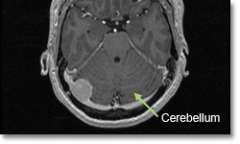

Location - Posterior Fossa (area where the cerebellum is)

Common Symptoms - Unsteadiness and incoordination, hydrocephalus (increased pressure inside the brain), voice and swallowing difficulties.

- Magnetic resonance imaging (MRI) scans effectively detect most meningiomas and are best at displaying details of the brain.